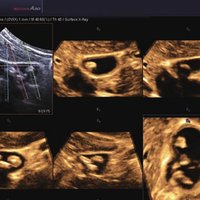

• FAD™, die Face Auto Detection, stellt das Gesicht eines Fötus besonders detailliert dar. Überflüssige Daten werden entfernt und ein besonders realistisches Bild gezeichnet.

• Volume Shade Imaging, kurz VSI™, visualisiert ein 3D-Bild, das Hauttöne und Schattierungen auf ein qualitativ neues Niveau hebt.